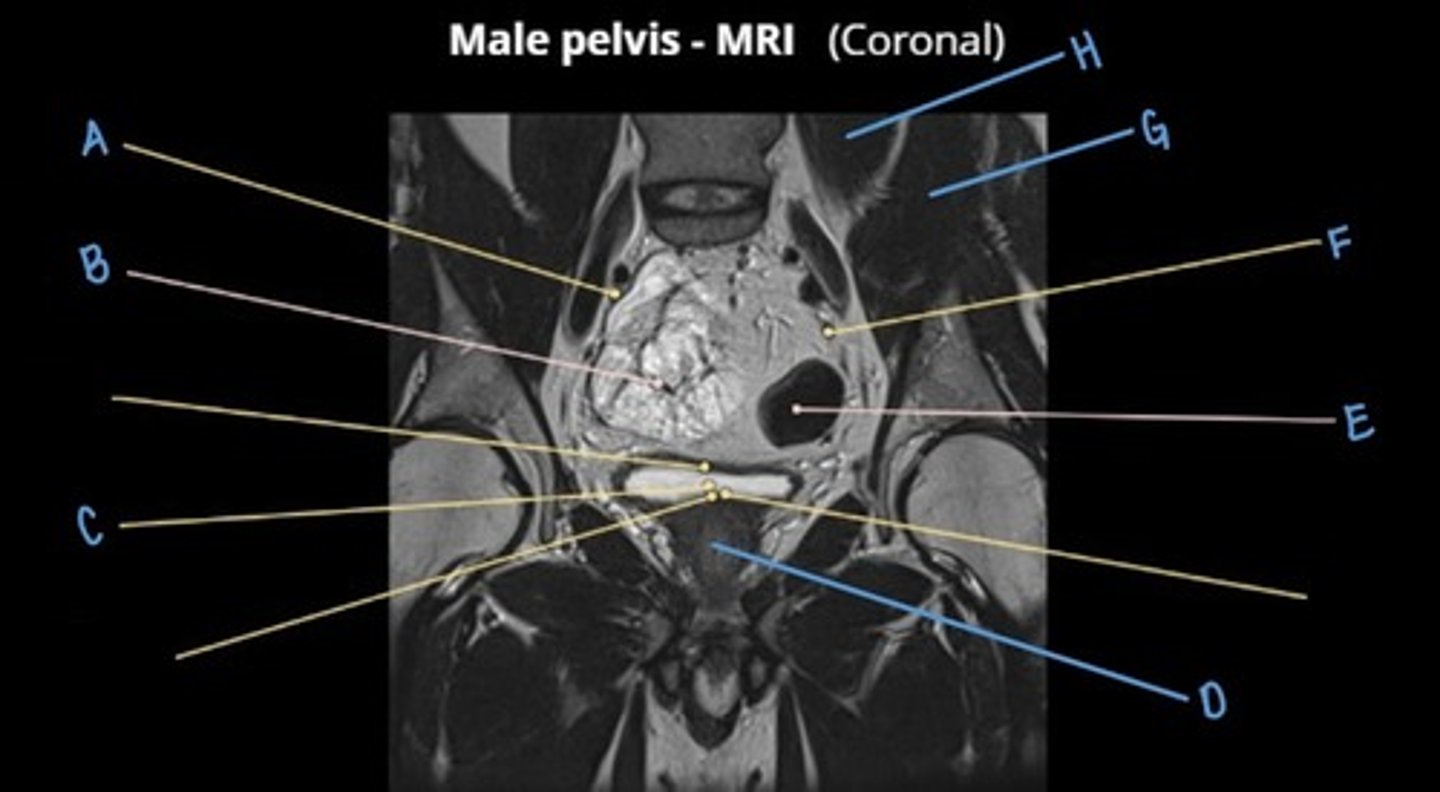

seminal vesicles

C

rectum

D

bladder

E

trigone of the bladder

F

obturator internus muscle

G

gluteus maximus muscle

H